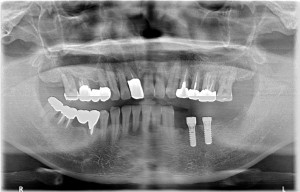

複数の歯に及び歯が失われているためCT画像上で診断と設計を行い、理想的な位置に歯を作ることができるように、サージカルガイドと言われるインプラント手術補助用マウスピースを用いてインプラント手術を行った。

手術の精度を更に上げるサージカルガイド

術前レントゲン写真

術後レントゲン写真